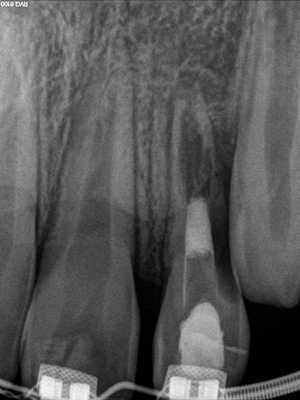

В течение последних двух десятилетий в стоматологической литературе была представлено значительное количество публикаций, описывающих уникальные случаи внешней резорбции полностью витальных зубов в области шейки. Следовательно, данную разновидность патологии пришлось добавить к двум уже ранее известным (фото 4). Иногда термины для описания данного вида поражения носят лишь субъективный характер, но для четкого понимания в данной статье будет использоваться название инвазивная пришеечная резорбция корня (ИПРК), поскольку именно такое название данной патологии дал доктор Geoffrey S. Heithersay, который и описал ее первично. В данной статье будет рассмотрены как клинические, так и рентгенологические признаки резорбции, а также аспекты, связанные с ее этиологией, патофизиологией и лечением.

Фото 4. Рентгенограмма, демонстрирующая пример инвазивной пришеечной резорбции.

Иногда поражение проявляется клинически очевидным образом. На фото 7-10 представлен случай, когда пациент сам отметил розовую дисколорацию в пришеечном отделе правого бокового резца. Хотя чувствительность пульпы была нормальной, было обнаружено перфорирующее поражение вдоль дистально-щечной стороны зуба. Хотя предварительно считалось, что наличие розовых дисколораций свидетельствует о внутренней резорбции зуба, на самом деле в большинстве таких случаев клинически диагностируют ИПКР.

Фото 7. Случай ИПКР в области 10 зуба с формированием розовой дисколорации.

Фото 8. Подтверждение диагноза ИПКР на рентгенограмме.

Фото 9. Подтверждение диагноза на КТ-срезе.

Фото 10. Распространение ИПКТ в парапульпарном апикальном направлении (срез КЛКТ).